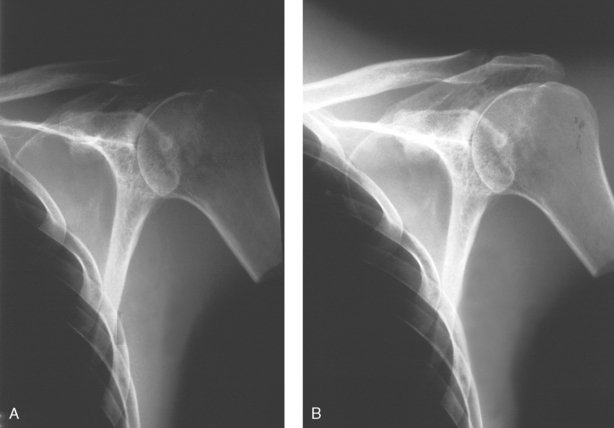

• The Boomerang filter was designed to conform to the shape of the shoulder and create images of more uniform radiographic density at the superior margins (Fig. 2-11). This is a contact filter placed between the anatomy and the IR (see Fig. 2-4, B). It can also be used effectively for lateral facial bone images. Although effective in compensating for differences in anatomic density, this filter does not reduce radiation exposure because it is located behind the patient. The Ferlic shoulder filter is a collimator-mounted filter also designed specifically to image the shoulder (Fig. 2-12). Because this filter is placed in the primary x-ray beam, it also acts to reduce radiation exposure to the patient.

Fig. 2-12 A, AP projection of shoulder without compensating filter. B, Same projection using Ferlic shoulder collimator mounted filter. Note greater visualization of acromion, acromioclavicular joint, and humeral head.